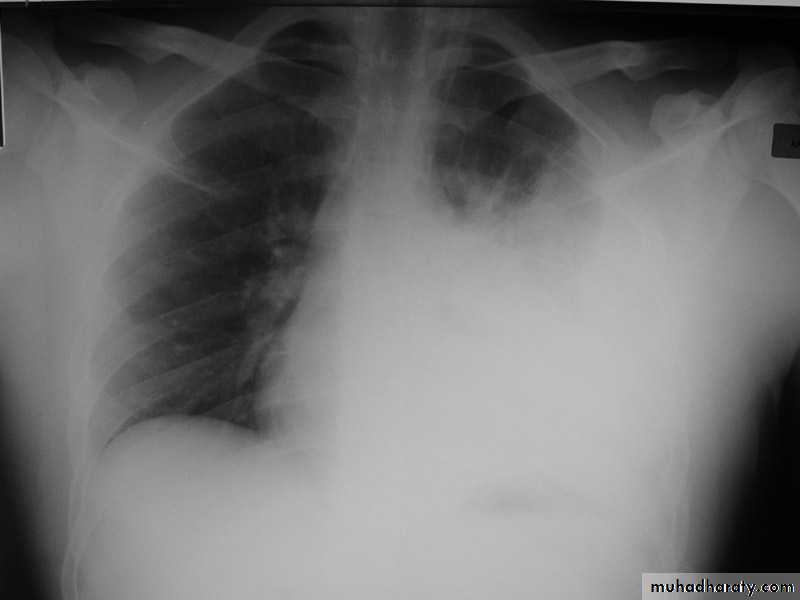

X-ray of pleural effusion

Massive right effusion